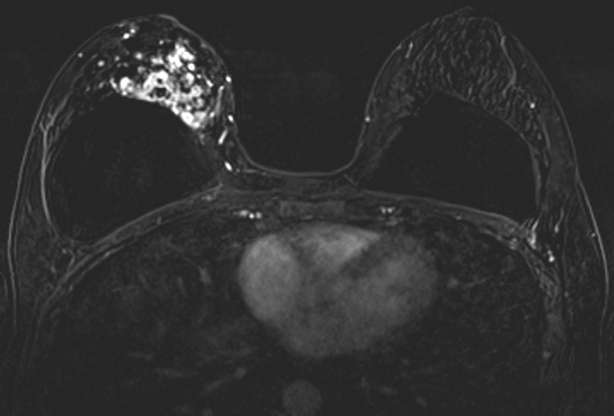

Biopsy-Proven IDC and DCIS as Segmental, Clustered Ring NME.

Figure 2. Biopsy-Proven IDC and DCIS as Segmental, Clustered Ring NME. Contrast-enhanced breast MRI, axial subtraction image demonstrates NME in the right breast with segmental distribution and clustered ring enhancement at 12-1 o’clock and abutting the s